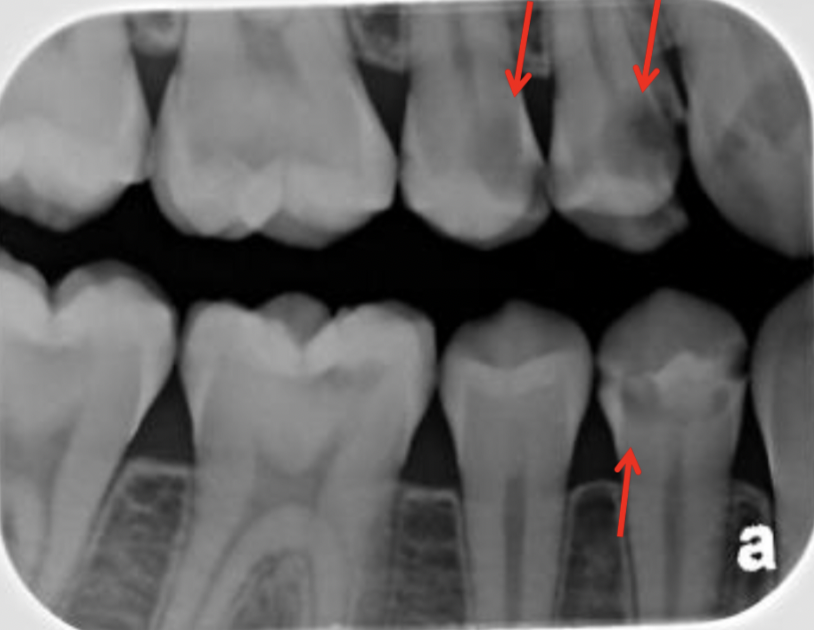

Q

Classify the caries

A

moderate caries (MC)